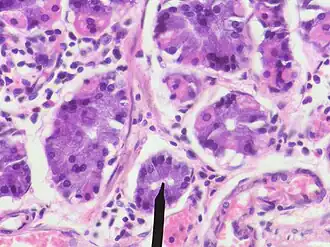

Human chief cells near tip of RED pointer

Chief cells are part of fundic gland polyps (here shown in high magnification).[13]